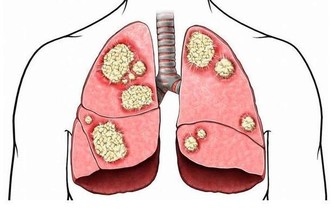

血脂,一聽到這個詞,很多人會聯想到心臟方面的症狀,

事實上,膽固醇不僅會堵塞心血管,還會引起外周動脈疾病,雙腿會直接出現症狀。